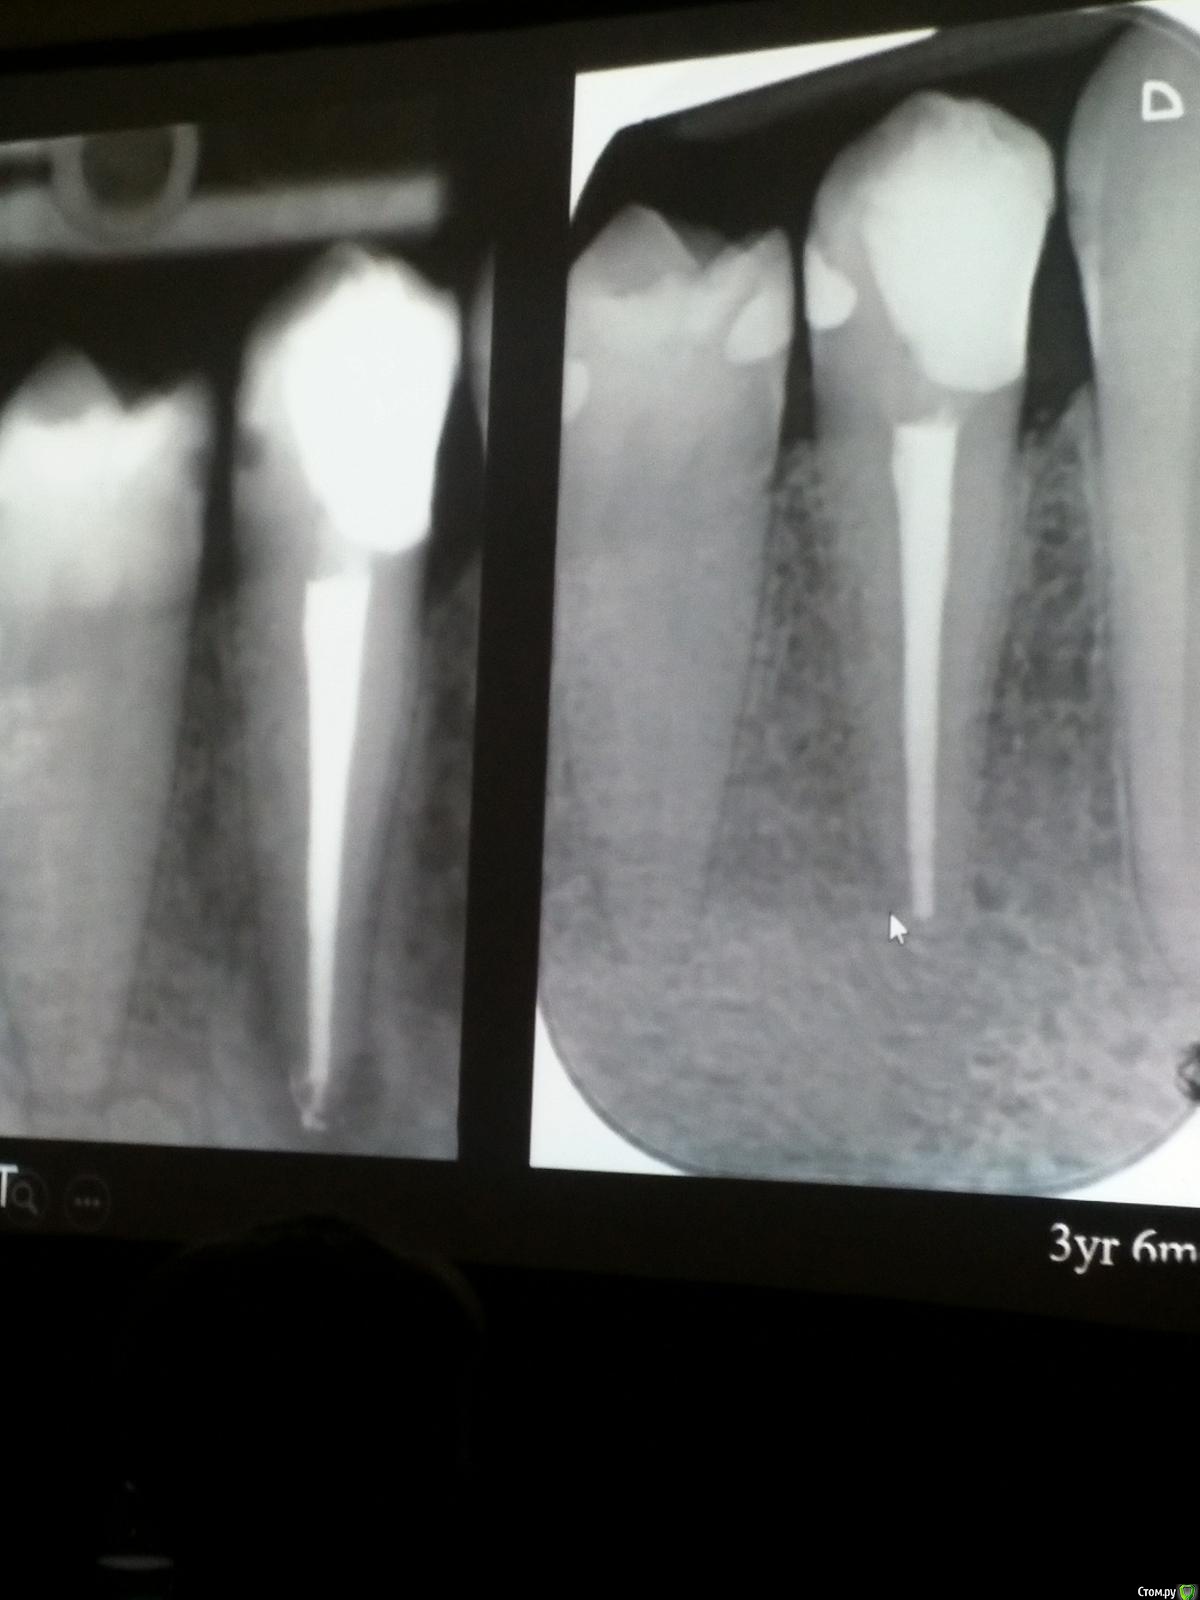

Популярный пост Kolchanov Опубликовано 12 марта, 2017 Автор Популярный пост Поделиться Опубликовано 12 марта, 2017 Второй день.1) Дезинфекция зуба и раббер дама перед работой. Вначале установка системы, потом протирка тампоном 30% перекиси, потом протирка всего йодинолом. Потом преп, потом повторение и только потом доступ к к/к. Все старые реставрации надо убрать, кариес убрать, противник лечения через коронку.2) Гидроокись на неделю. Замешивает на стерильном физрастворе. При необходимости повторяет. Т.е. в случае сохранения свища, симптоматики, экссудации, запаха. Если свищ не исчезает после трех смен временных вложений, то хирургия.3) Пломбирует латеральной компакцией. Лучше контроль длины обтурации.4) Высушивание канала стерильными штифтами, на рабочую длину минус 1мм. После высушивания штифт оставляется на 60с. в канале и должен выйти сухим.5) Определение рабочей длины. Витальные случаи. АЛ должен три раза дать одну и ту же картинку в определенной точке + проверка RG. Девитальные случаи. На АЛ полагаться сложно, т.к. из-за наличия резорбции констрикции может врать, больше ориентируется на RG.6) Использует ЦОЭ силеры. Резорбируются при незначительном выведении. Резорбируются в канале, позволяя закрыть апекс цементоподобной тканью. Вот так вот.Случаи исчезновения силера, как за пределами канала так и в канале7) Выведение материала (не важно какого) в большом объеме способно вызвать защитную реакцию тканей. Которая должна пройти спустя некоторое время. (иногда это будет 25 лет J Случай 1ый. Студенты наломали инструментов. Периодонтит на RG через год. Резекция и гистология. Бактерий не обнаружил. Да, маленькое замечание. Каждый препарат дает 500-600 срезов. И ищет он на всех. Объем работы, конечно….Случай 2й. Его собственный. Периапикальное поражение, обнаруженное на реколле через 10 лет зажило еще через 15.8) «Функционирующий зуб» считает результатом неприемлемым. Осталась инфекция с которой надо что-то делать. То, что бактерий можно замуровать в дентинных трубочках и под пломбировочным материалом, считает неправильным. Продукты метаболизма один фиг будут просачиваться и могут поддерживать реакцию воспалительную.Случай. Синее – маленькая кучка микробов, предположительно, препятствовавших заживлению очага.9) Биопленка на поверхности корня может принимать вид кальцификатов (камней) и тут уже только хирургия в помощь. При длительном существовании свищевого хода, например.Черное - это камни вокруг апикального отверстия. И гистология их с кучей синих микробов.Здесь камни на фуркации и отсутствие заживления и свищ даже после ретроградной обработки и пломбировки.А здесь вообще чертова уйма камней. И зацените разветвление канала в этом боковом резце (последнее фото препарата). 10) Реваскуляризация.В некротических случаях дентина не образуется, т.к. одонтобластов нет и не будет новых. Образуется та самая бог знает какая ткань, которая даже и с корнем не связана может быть. Суть здоровый дентикль-петрификат. А в витальных это не реваскуляризация, а обычное формирование корня. Так что нечего тут.11) Трещины дентина.Советует расшивать, братья и сестры. Без фанатизма, если нет симптоматики, но, по возможности максимально. Если есть симптоматика, то там уже по обстоятельствам. Чертова уйма микробов там и ползет, ползет к пульпе. Надеюсь, что еще раз этот замечательный Доктор приедет. Схожу с удовольствием. 2 23 Ссылка на комментарий

Популярный пост Kolchanov Опубликовано 11 марта, 2017 Популярный пост Поделиться Опубликовано 11 марта, 2017 (изменено) Товарищи, скажу я вам...........Вкратце. Может я где-то что-то и приврал, надеюсь, кто еще был, поправят. Честно говоря немного прибалдел от уровня Доктора. Очень, очень высоко! Приедет еще раз, пойду еще. 1) Фиссуры зондирует острым зондом и выпиливает все дотла. По факту у него уже пломбы, а не герметизация.2) Bite-wing у первичных пациентов всегда.3) Если кариес диагносцирован, то лечить его, пофиг какой он там. Эмали, дентина…4) Препарирует до твердого (или до вскрытия J ). CAD, СID… в топку. Кариес маркером не пользуется, проверяет острым зондом/экскаватором. Вычищает все дотла. Считает, что даже небольшое количество бактерий в дентине под пломбой вызывают хроническое воспаление в пульпе. С его слов у него на контроле где-то 500 вскрытий, не удивительно при таком подходе к очистке.5) Тщательная изоляция. Коффер порвался – меняет. Большое значение герметичности реставрации. под замену6) Критерии обратимости и необратимости.Гистологически, обратимый тот, что без абсцессов в пульпе, но клинически это понять нельзя, только предположить.Здесь был бы обратимый, если бы не удалил. Нет микробов в пульпе. Линия - граница обработки.Покрытие 27 лет назад. Dycal, СИЦ, композит. От дайкала одно воспоминание.7) Вскрылись. Размер перфорации, возраст и прочее не играют роли, важно только состояние пульпы, т.е. диагноз.Примеры перфораций.8) Кровотечение останавливает стерильным ватным шариком. Если останавливается, то покрытие, если нет, то пульпотомия или пульпэктомия.9) Использует гидроокись кальция (порошок), перекрывает Dycal или СИЦ. Потом восстановление Нередко под IRM, потом все убирает (через пару-тройку месяцев) и смотрит, что получилось. Порой приходится повторять! Использует и МТА, его тоже убирает.10) Наблюдение 6мес, 1 год, 2…. Все может провалиться и через месяц и через 24 года.Примеры проваловНиже - 24 года спустя появилась дуля. 11) Неравномерная облитерация полости зуба на RG (после покрытия) – признак текущего хронического воспаления, где-то остались микробы. Рекомендует эндо.12) Мостик который образуется – это не дентин! И одонтобласты не регенерируют и новые не образуются. Что это такое он и сам не знает, но раз это твердые ткани, то и наплевать.Вот фиолетовое это дентинные опилки вмурованные в розовую ткань бог знает кем сформированную.13) Пульпотомия в зубах с несформированной верхушкой и в сформированных, при подозрении на частичное поражение коронковой пульпы. Иссекается стерильным алмазным бором часть пульпы, гидроокись, временная пломба на 90 дней, после повторное раскрытие, оценка результата, восстановление в случае формирования твердых тканей. Гипохлоритом можно мыть, можно не мыть, если мыть, то 0,5-1%.14) В апикальной части пульпа чаще витальна, чем нет.15) Периапикальные поражения возникают по причине поступления токсинов микробов с током крови, а не самих бактерий.16) За апикальные расширения в полностью некротических случаях. Надо механически отодрать биопленку и срезать инфицированный дентин. На ирриганты надежды мало.17) Биопленка на поверхности в 6% случаев.Синенькие пид@расы18) Обработку проводить нежно, краун-даун. Чередовать с H-файлом, чтобы посмотреть докуда распространяется некроз.19) Патенси в витальных кейсах не колоть, сохранять витальную пульпу в констрикции!Формирование еще большего сужения в констрикции за счет сохранения витальной пульпы. Изменено 11 марта, 2017 пользователем Kolchanov 31 Ссылка на комментарий